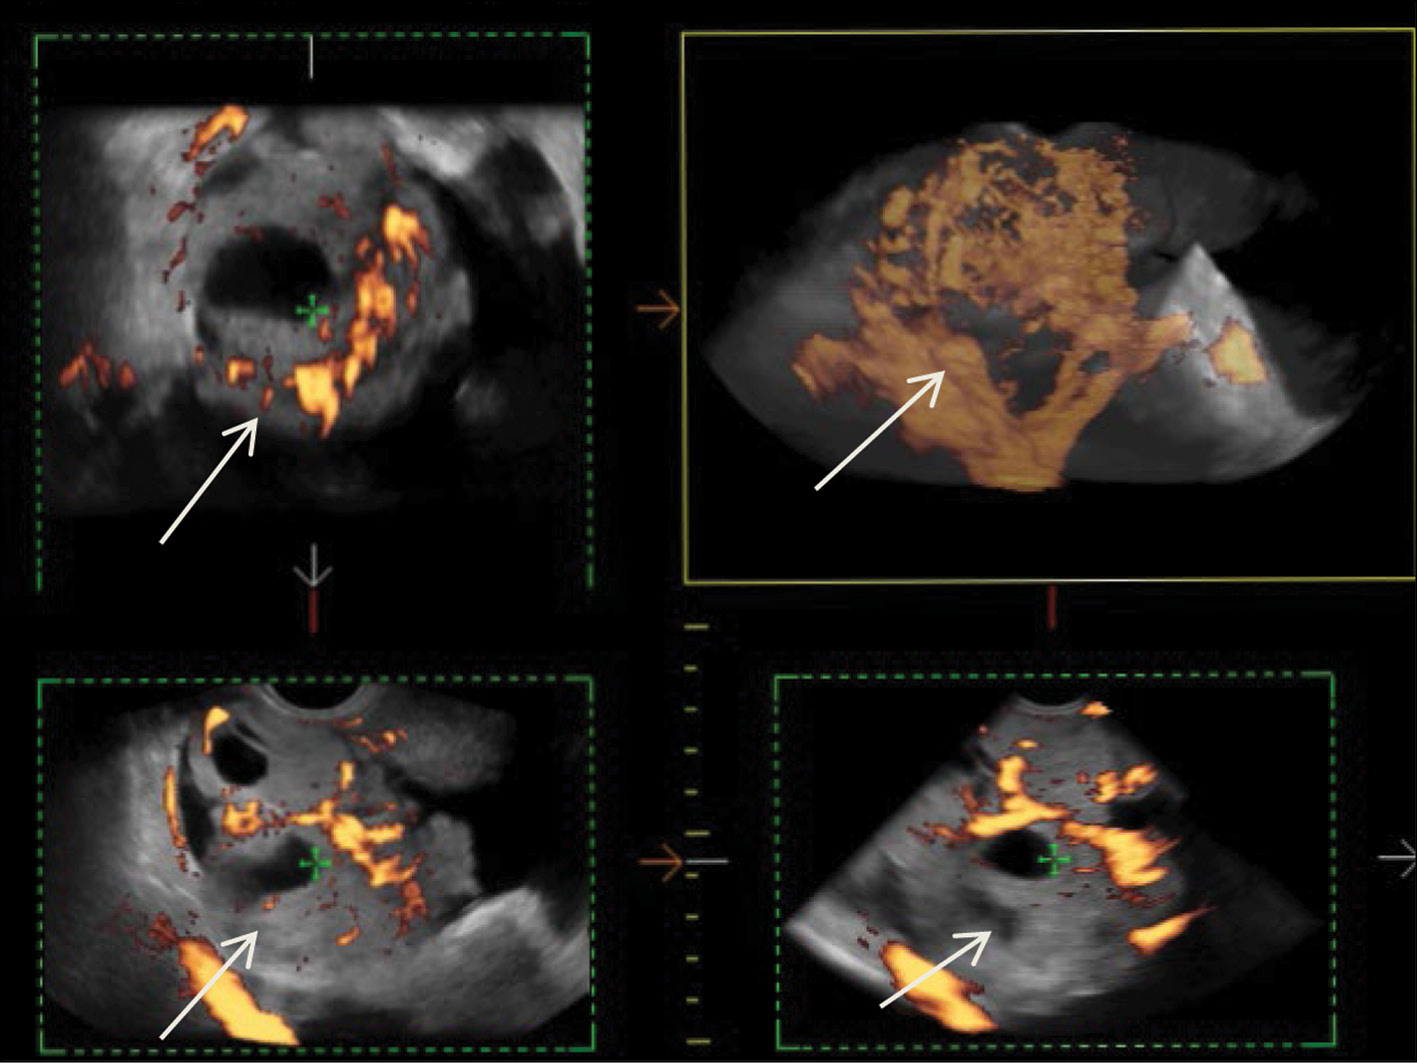

US demonstrated that the recurrent lesion of malignant struma ovarii along the pelvic peritoneum, identified in the presence of ascites, had an iso-hypoechoic structure with fuzzy contours and small size (4–12 mm). The peritoneum of the small pelvis outside the lesion was <4 mm thick; however, 3D angiography and US-CT revealed that even small blastomatous lesions were well vascularized. Blood flow was also present in the 4–5 mm thick structure of the pelvic peritoneum (Figs. 5–7).

Fig. 7. 3D angiography of the recurrent lesions of the malignant struma ovarii in the pelvic peritoneum in the presence of ascites.

To identify specific US signs of malignant struma ovarii, recurrent tumor lesions along the peritoneum of the malignant struma in one patient were compared with recurrent lesions of serous ovarian adenocarcinoma in 12 patients. When comparing the tumor lesions in the retrouterine space, a more pronounced neoangiogenesis was noted in the tumor lesion of the malignant struma ovarii, where the peak systolic velocity (PS) was recorded in small lesions (4–12 mm) and ranged from 2 to 9 cm/s. The maximum vascular resistivity index (RI max) was 0.53. No blood flow was noted in recurrent lesions along the pelvic peritoneum of the serous adenocarcinoma up to 9 mm, and in lesions up to 15–20 mm, PS varied from 2 to 4 cm/s or was <2 cm/s (Figs. 5 and 8).